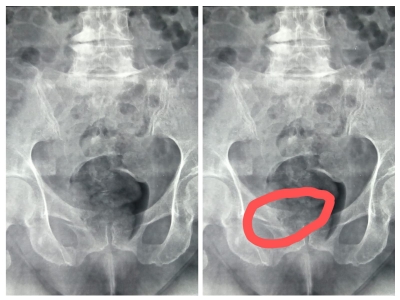

Por volta das 10:00, chegou dona Juscelina. Saiu do táxi com dificuldade, amparada pelo motorista. Caminhava com muita dor. Pediu para usar o banheiro. Aproveitei para dar uma olhadinha na única incidência radiográfica (AP da pelve). Meus olhos foram escaneando a imagem. Estava procurando inicialmente por alguma fratura compressiva em T11, T12 ou possivelmente L1. Mas a imagem cortava em em L4. Havia uma área de esclerose e importantes sindesmófitos laterais à direita de L4/L5. Mas isto já tinha visto antes nas outras radiografias antigas da paciente. As articulações coxo-femorais exibiam alguma osteoartrose. Havia também muito gás e material fecal. E outras coisinhas mais. Foi então que eu notei o ramo superior do púbis. Custei a acreditar no que via, considerando que o exame de imagem tinha sido laudado pelo radiologista e visto por um ortopedista e por uma fisioterapeuta.

Havia ali uma patente e óbvia fratura.

Meio desapontada, nossa heroína entrou de volta no táxi e seguiu para o centro da cidade. Lhe mandei por whatsapp uma foto da radiografia com a área da fratura assinalada seguida pelas seguintes mensagens:

QUIROPRAXISTA — Juscelina, olhando essas imagens um pouco melhor, é bom procurar (o) ortopedista ainda hoje. Ele deve pedir uma tomografia para avaliar a extensão da fratura.

QUIROPRAXISTA — O ramo superior do púbis definitivamente está fraturado. Talvez haja uma fissura no ramo inferior do púbis também. Daí a importância da TC.

Abaixo segue a radiografia para apreciação dos colegas: